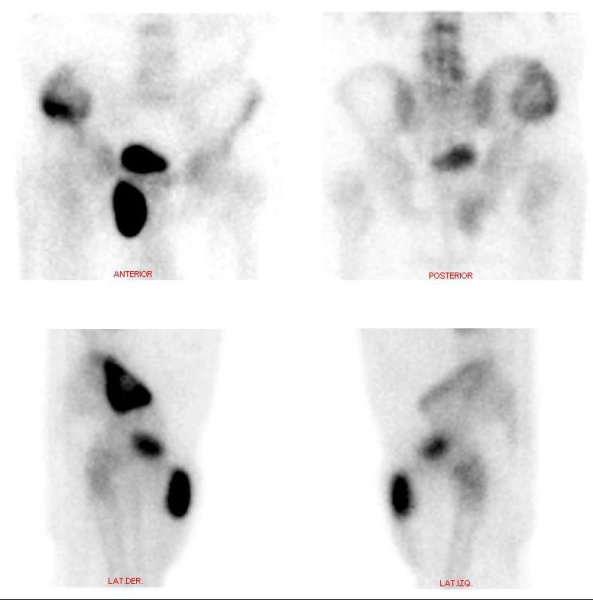

Se presenta el caso de un paciente masculino de 70 años con un único antecedente de carcinoma basocelular invasivo previamente operado, al cual le es solicitado un centellograma óseo debido a una lesión en alerón ilíaco derecho reportada en una tomografía computarizada (TC) de pelvis. Se realiza rastreo de cuerpo completo con 99mTc-MDP, imágenes estáticas de pelvis y SPECT. En el estudio de cuerpo completo se observó lesión en cresta ilíaca derecha, hipercaptante con componente lítico central, junto con un foco de hipercaptación de intensidad similar a la vejiga, proyectado por debajo de la rama superior del pubis derecho, de aspecto sacular (fig. 1). En las imágenes segmentarias con vistas anteroposteriores y laterales se evidencia que el hallazgo es de ubicación anterior respecto a la rama isquiopubiana derecha (fig. 2). En el estudio SPECT se confirma una gran lesión hipermetabólica con área central fotopénica de aspecto redondeado, que protruye de la cresta iliaca derecha y no respeta bordes anatómicos. Además, se evidencia claramente la existencia de conexión entre la vejiga y la zona hipercaptante de aspecto sacular ya mencionada (figs. 3 y 4).